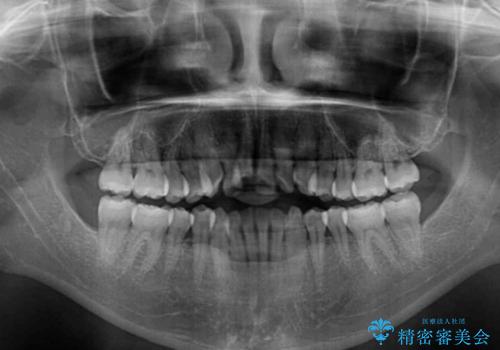

- 前歯のデコボコと上下が開いていることを気にして来院された患者様です。

いわゆるオープンバイトは、インビザラインによる治療が適しているため、インビザラインにて治療を行うこととしました。